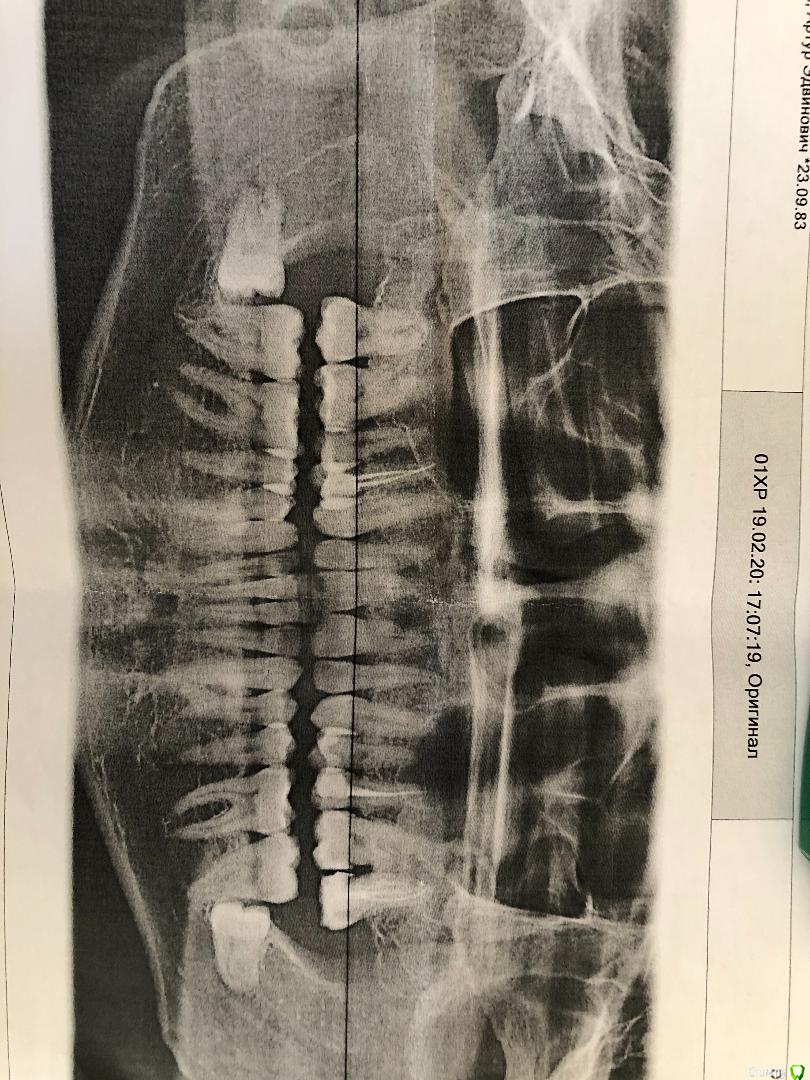

Archie Опубликовано 29 марта, 2020 Поделиться Опубликовано 29 марта, 2020 Добрый день! Хотел бы попросить рекомендации по плану лечения от присутствующих здесь докторов. Ранее в этом месяце планово удалял одну из восьмерок - внизу слева. Перед удалением 8ки сделали КТ, и обнаружилась проблема еще в 7м зубе на верхней челюсти с левой стороны. Зуб был сильно разрушен в свое время, мне удалили нервы и поставили штифты, на которые нарастили пломбу. Сейчас, как я понял, из-за этого зуба у меня образовалась воспалительная полость. Хотел бы получить Ваши рекомендации касательно возможных вариантов лечения - стоит ли пытаться лечить, или необходимо удалять... И если удалять - то как лечится воспалительная полость... Прикладываю фото панорамного снимка, а также ссылку на КТ: Ссылка для скачивания файлов: https://cloud.mail.ru/stock/memDsTvYXZ9bRsFwgr122GGE Заранее благодарю за рекомендации. Ссылка на комментарий

Archie Опубликовано 5 апреля, 2020 Автор Поделиться Опубликовано 5 апреля, 2020 Спасибо за ответ! Я так понял, проблема «под» зубом. Как мне сказали: на 1 из корней 27 зуба имеется перфорация с резорбцией плюс огромный воспалительный очаг в области корней ,зуб подлежит удалению и не подлежит лечению. Иногда побаливает, не постоянно, скорее эпизодически «дергает». Ссылка на комментарий